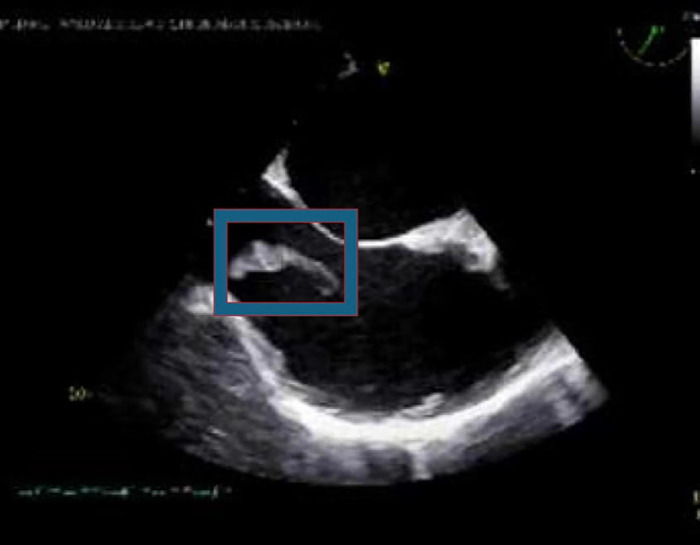

Case presentation: A 45-year-old male patient was admitted into the surgical intensive care unit with Fournier's gangrene, septic shock, and acute kidney injury (AKI). The patient was managed by invasive ventilation, noradrenaline, vasopressin, and renal replacement therapy. He developed Escherichia coli bacteremia and candidemia. We added meropenem and antifungal to the therapy. The transthoracic echocardiography showed EV vegetation and thread-like vegetation in the right coronary sinus, which was confirmed with transesophageal echocardiography. With aggressive therapies, the patient recovered from septic shock, organ dysfunction and was successfully liberated from invasive ventilation. The patient was discharged home on day 27. The antibiotics and antifungal were continued for 6 weeks. Two weeks after discharge, the follow-up echocardiogram was normal, and he was doing well.